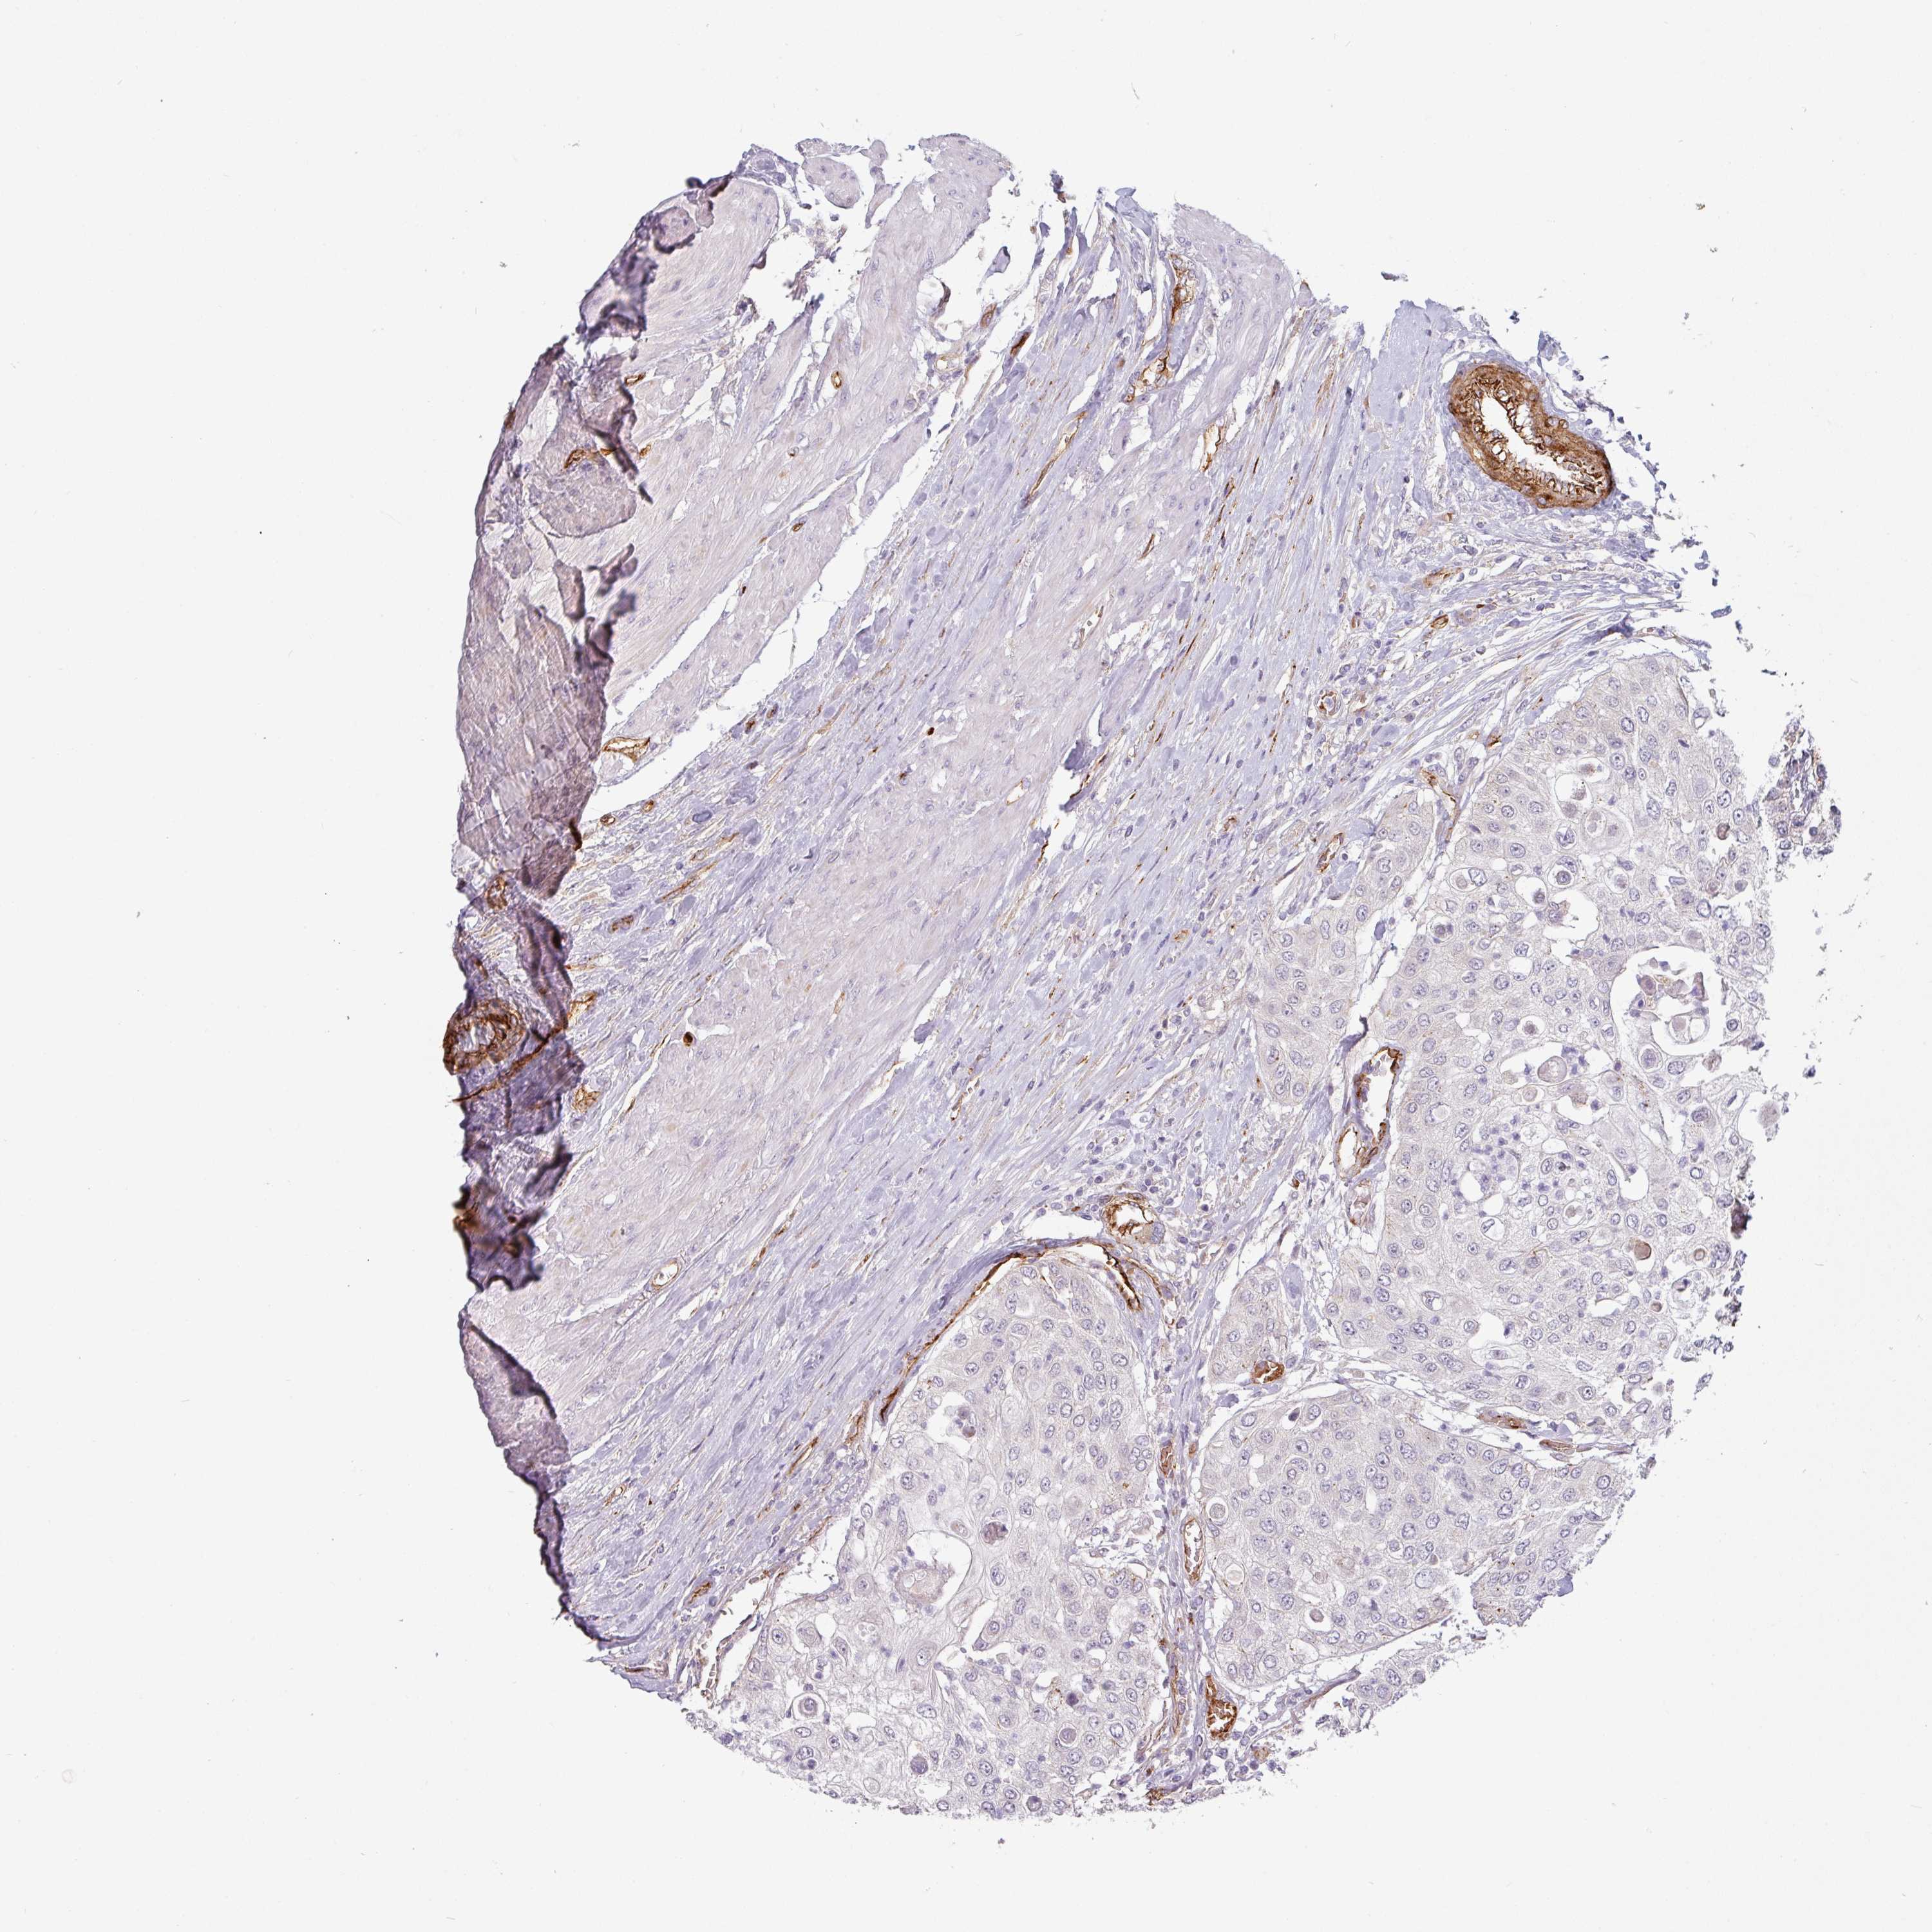

UROTHELIAL CANCER - Protein expressioni

A mouse-over function shows sample information and annotation data. Click on an image to view it in a full screen mode. Samples can be filtered based on level of antibody staining by selecting one or several of the following categories: high, medium, low and not detected. The assay and annotation is described here.

Note that samples used for immunohistochemistry by the Human Protein Atlas do not correspond to samples in the TCGA dataset.

Antibody stainingi

Antibody staining in the annotated cell types in the current human tissue is reported as not detected, low, medium, or high, based on conventional immunohistochemistry profiling in selected tissues. This score is based on the combination of the staining intensity and fraction of stained cells.

Each image is clickable and will lead to virtual microscopy that enables deeper exploration of all samples and also displays staining intensity scores, fraction scores and subcellular localization as well as patient and tissue information for each sample.

Antibody HPA051287

Staining

High

Medium

Low

Not detected

Intensity

Strong

Moderate

Weak

Negative

Quantity

>75%

75%-25%

<25%

None

Location

Nuclear

Cytoplasmic/membranous

Cytoplasmic/membranous,nuclear

Urothelial carcinoma, High grade

Urothelial carcinoma, Low grade